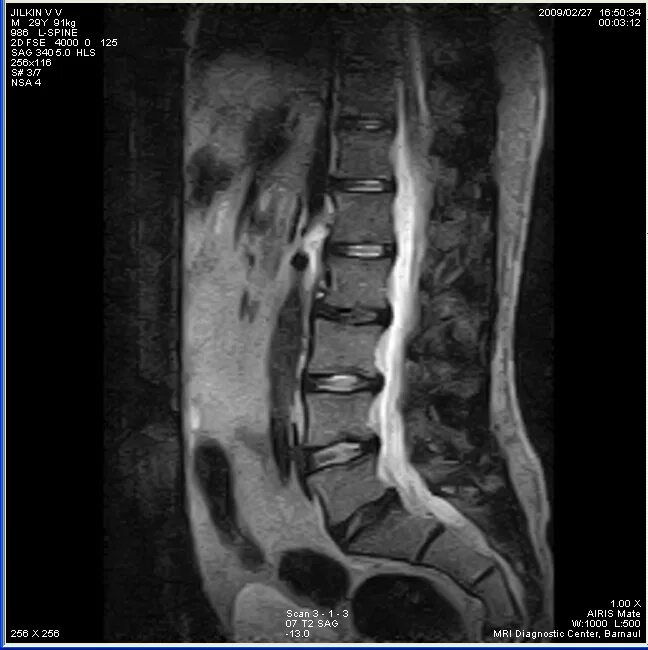

Мрт пояснично крестцового отдела тазобедренные суставы